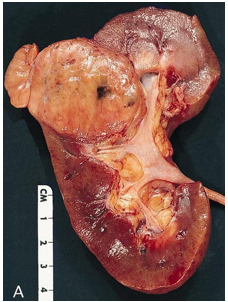

Đại thể

Thường là khối u vỏ thận một bên và đơn ổ, kích thước trung bình khoảng 7 cm. Khối u thường có ranh giới rõ, được bao quanh bởi giả bao u, phát triển theo kiểu đẩy nở và lồi ra từ vỏ thận. Hình thái đại thể đa dạng với thành phần đặc và nang, kèm các vùng xơ hóa màu xám và các ổ xuất huyết mới hoặc cũ màu nâu; hoại tử và biến đổi nang gặp thường xuyên. Khối u có màu vàng ánh kim do hàm lượng lipid cao; các khối u có độ mô học cao hơn có thể không có màu vàng do hàm lượng lipid và glycogen thấp hơn. Các vùng mềm, dạng thịt có thể phản ánh sự hiện diện của biệt hóa dạng sarcomatoid. Thường xuyên ghi nhận xâm lấn tĩnh mạch thận và xoang thận. Tổn thương hai bên và đa ổ là đặc điểm gợi ý bệnh lý di truyền.

Hình 2. ccRCC đã xâm lấn mạc Gerotta (pT4)

Hình 3. ccRCC có màu vàng, giới hạn ở thận (pT1b)

Hình 4. ccRCC đa ổ, với diện cắt đại thể loang lổ,khối u màu vàng óng xen kẽ các vùng xơ hóa và xuất huyết. Các vùng mềm, dạng thịt, màu nâu nhạt đến trắng xám trong khối u có thể gợi ý sự biệt hóa sarcomatoid.